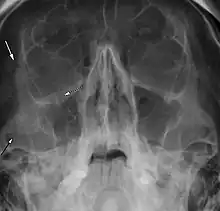

| Right zygomaticomaxillary complex fracture with disruption of the lateral orbital wall, orbital floor, zygomatic arch and maxillary sinus. | |

The zygomaticomaxillary complex fracture, also known as a quadripod fracture, quadramalar fracture, and formerly referred to as a tripod fracture or trimalar fracture, has four components, three of which are directly related to connections between the zygoma and the face, and the fourth being the orbital floor. Its specific locations are the lateral orbital wall (at its superior junction with the zygomaticofrontal suture or its inferior junction with the zygomaticosphenoid suture at the sphenoid greater wing), separation of the maxilla and zygoma at the anterior maxilla (near the zygomaticomaxillary suture), the zygomatic arch, and the orbital floor near the infraorbital canal.